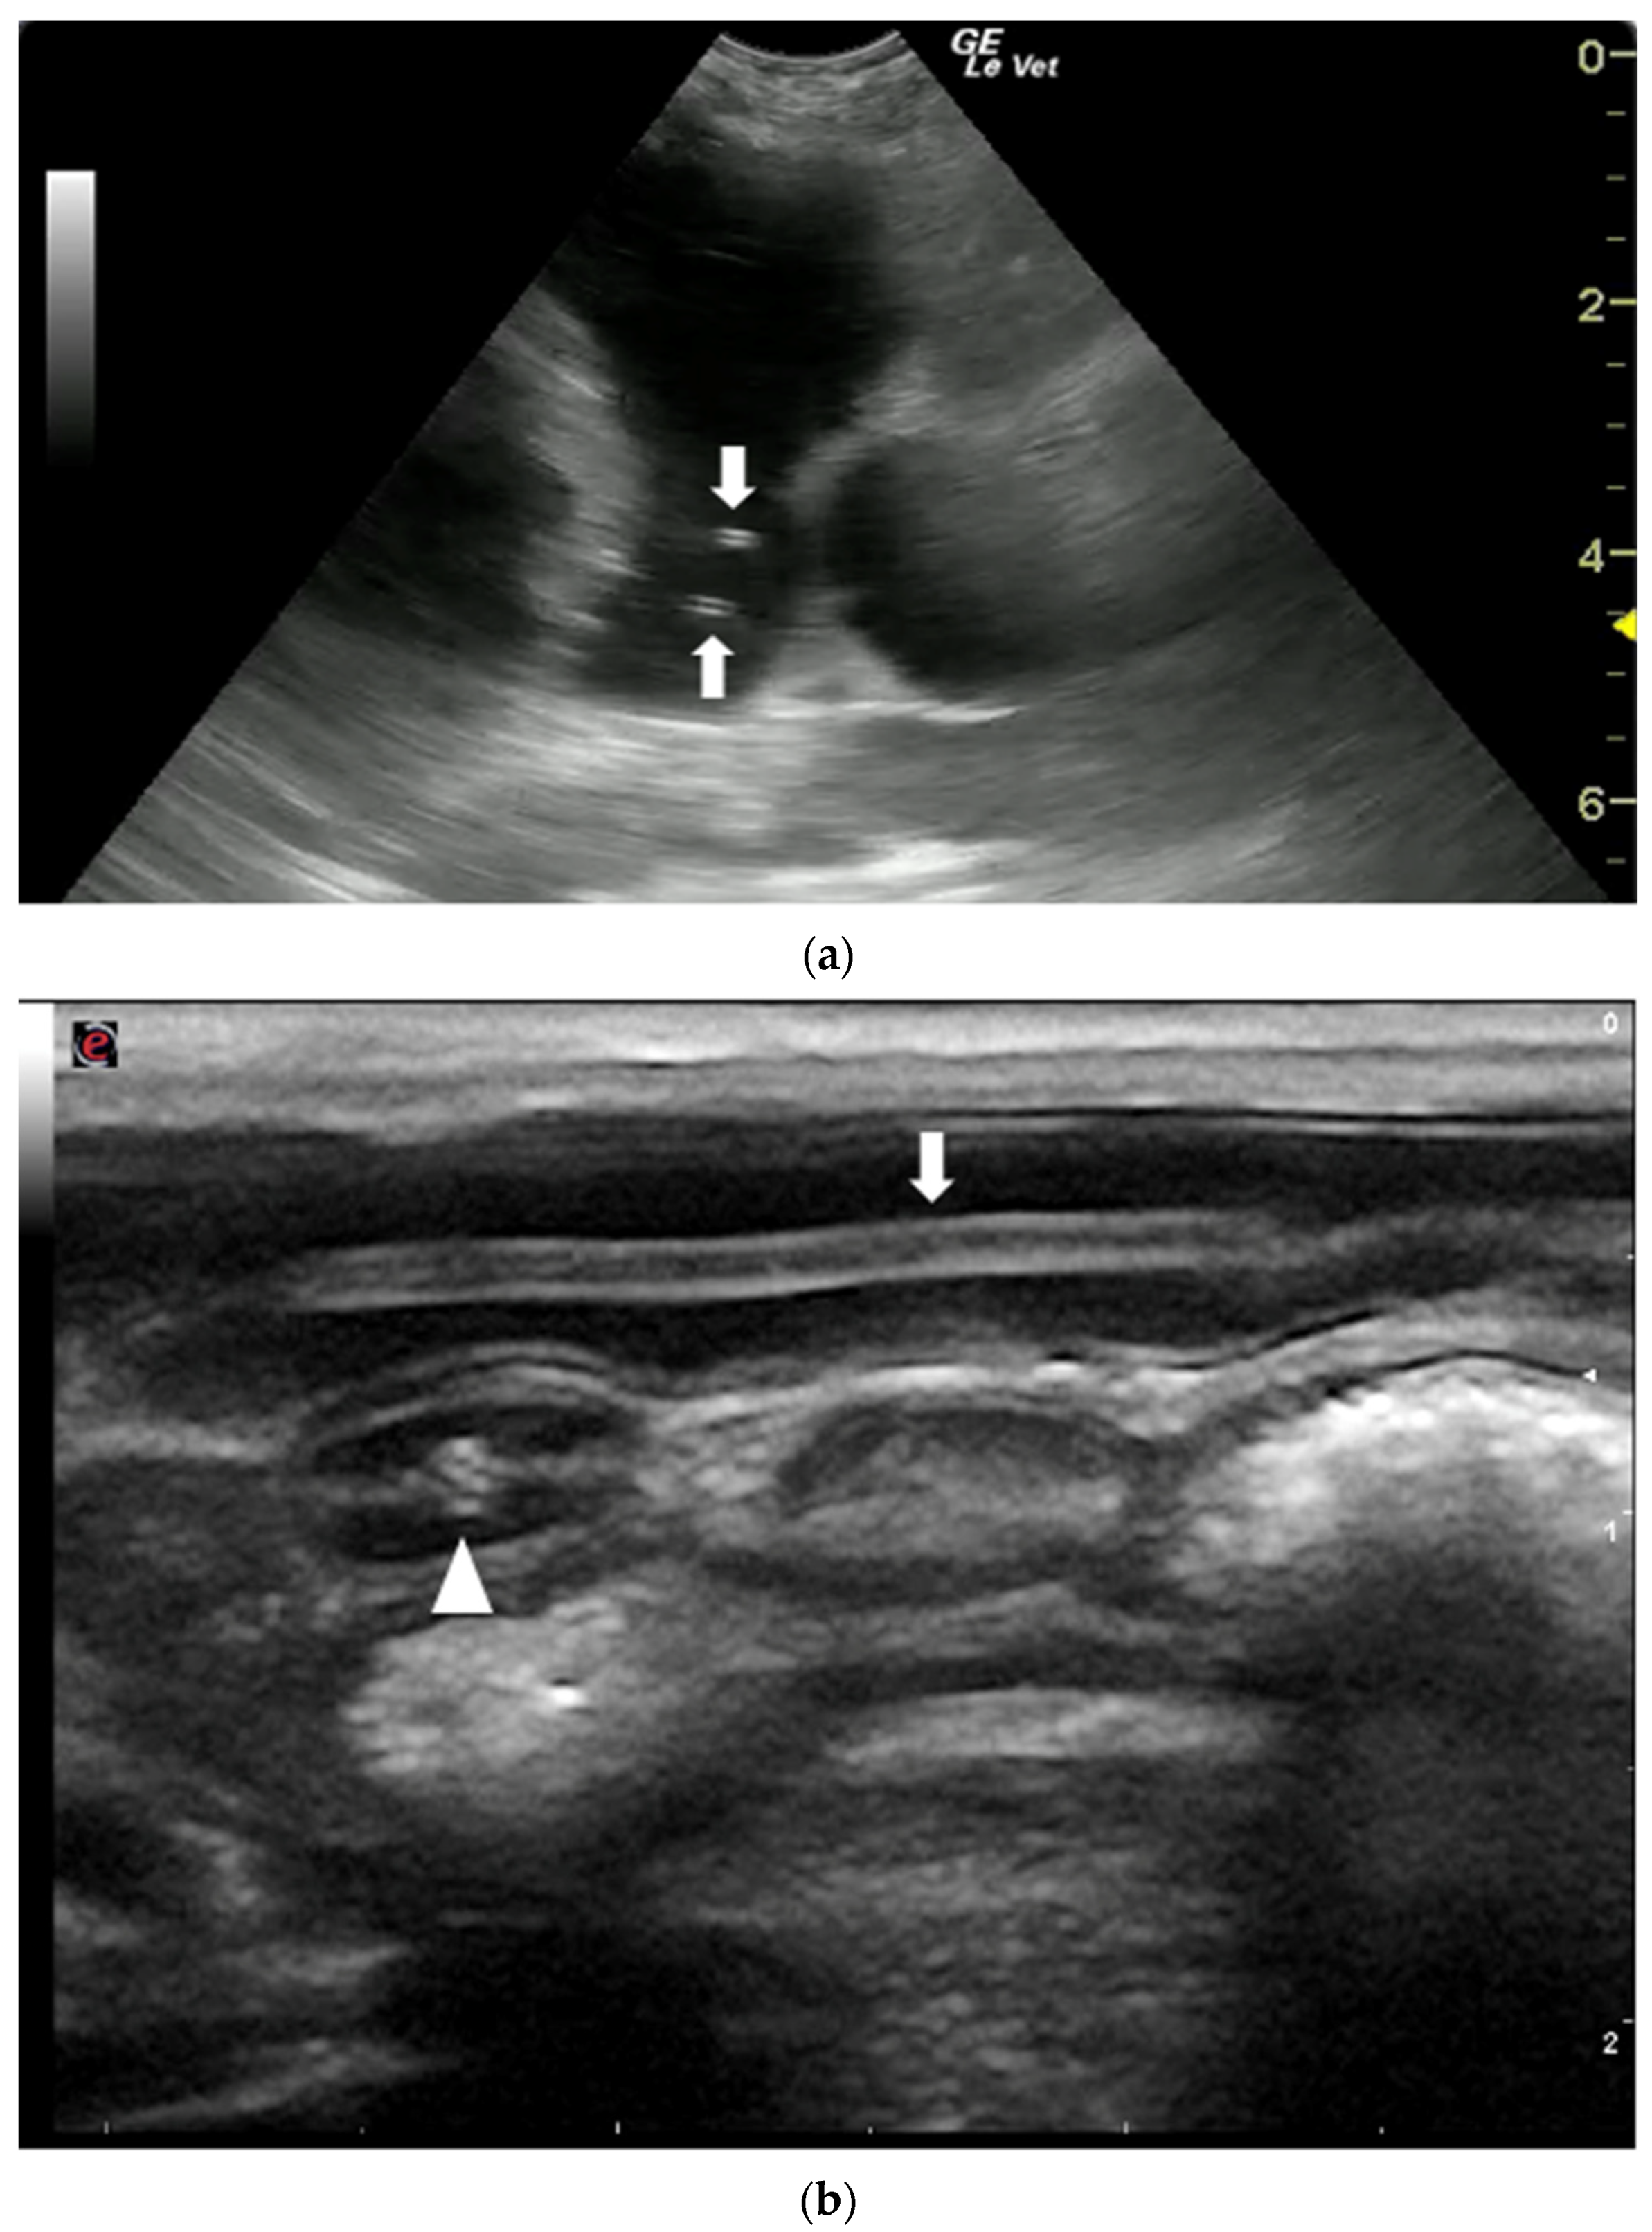

- Franchini, D.; Giannelli, A.; Di Paola, G.; Cortes, H.; Cardoso, L.; Lia, R.P.; Campbell, B.E.; Dantas-Torres, F.; Lenoci, D.; Assad, E.A.; et al. Image diagnosis of zoonotic onchocercosis by Onchocerca lupi. Vet. Parasitol. 2014, 203, 91–95. [Google Scholar] [CrossRef]

- Merhavi, N.; Segev, G.; Dvir, E.; Peery, D. Ultrasonography is insensitive but specific for detecting aortic wall abnormalities in dogs infected with Spirocerca lupi. Vet. Rec. 2020, 187, e59. [Google Scholar] [CrossRef]